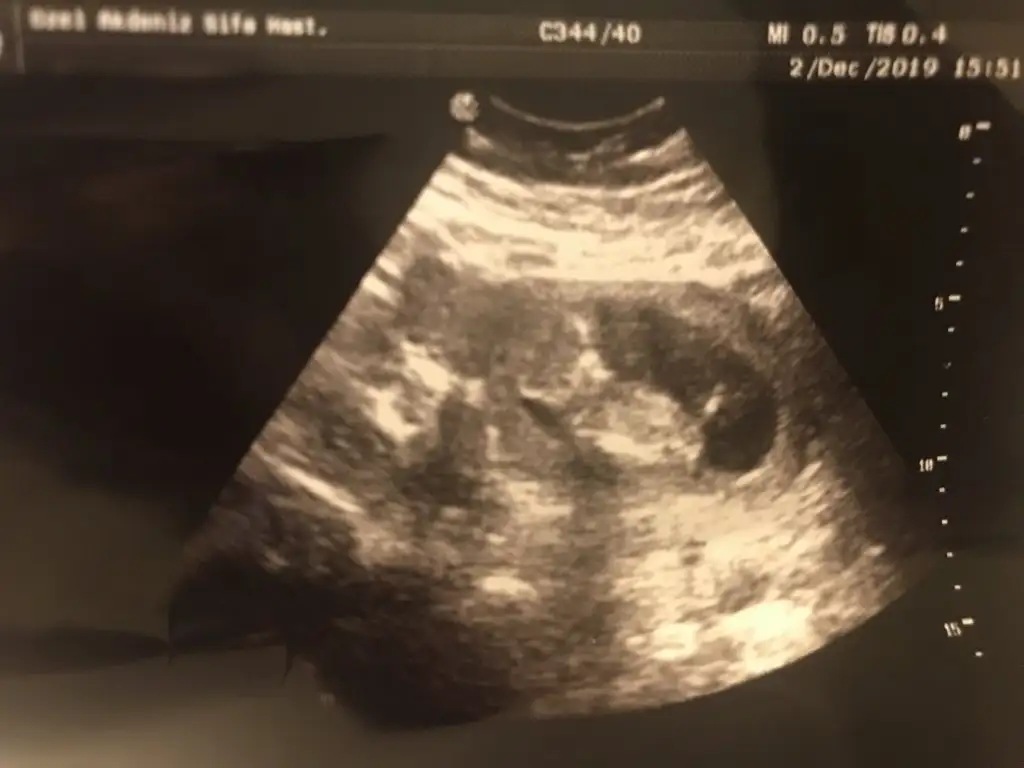

Erkek bebişarkadaşlar merhaba 12.hafta görüntüsü bebeğimin doktor erkek gibi konuştu ama net birşey demedi sizin tahmininiz nedir?Eki Görüntüle 2560931 Eki Görüntüle 2560931

teşekkürler bana da öyle geliyor bacak arası çıkıntı çok belirgin gibiErkek bebiş